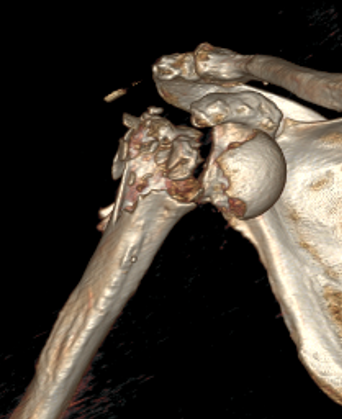

Severe comminuted proximal humerus fractures

100% displaced / off ended

Fracture - dislocations

- comminuted, 3 or 4 part

- head spltting fracture

- off ended / 100% displaced

Unreconstructable fracture - 4 part, comminuted, head spltting fracture